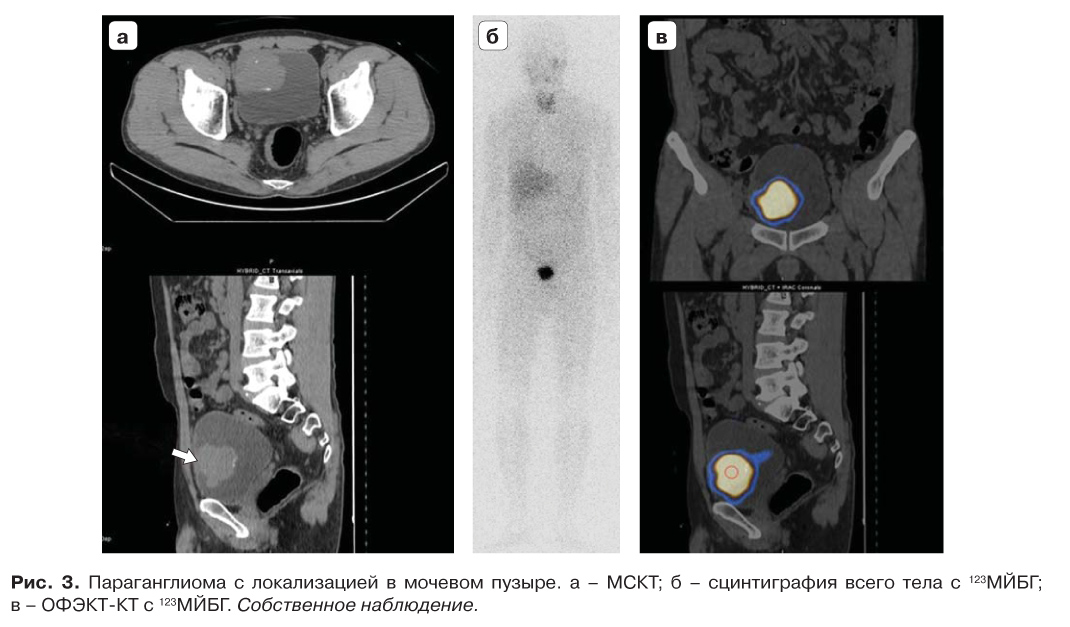

10. Fig. 3. Paraganglioma with localization in the bladder. a - MSCT; b - whole body scintigraphy with 123MyBG; c - SPECT-CT with 123MBG. Own observation. | |